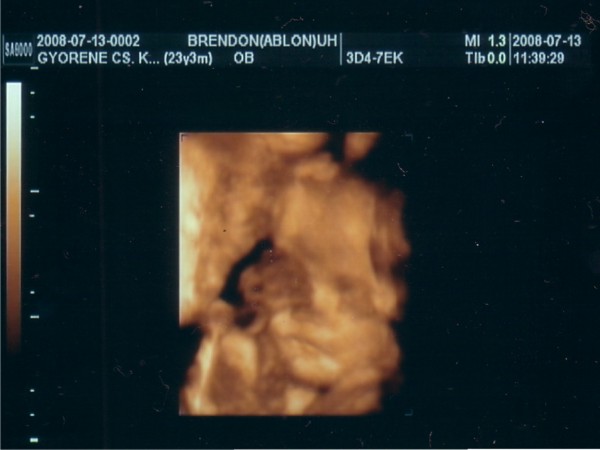

a Kistesók